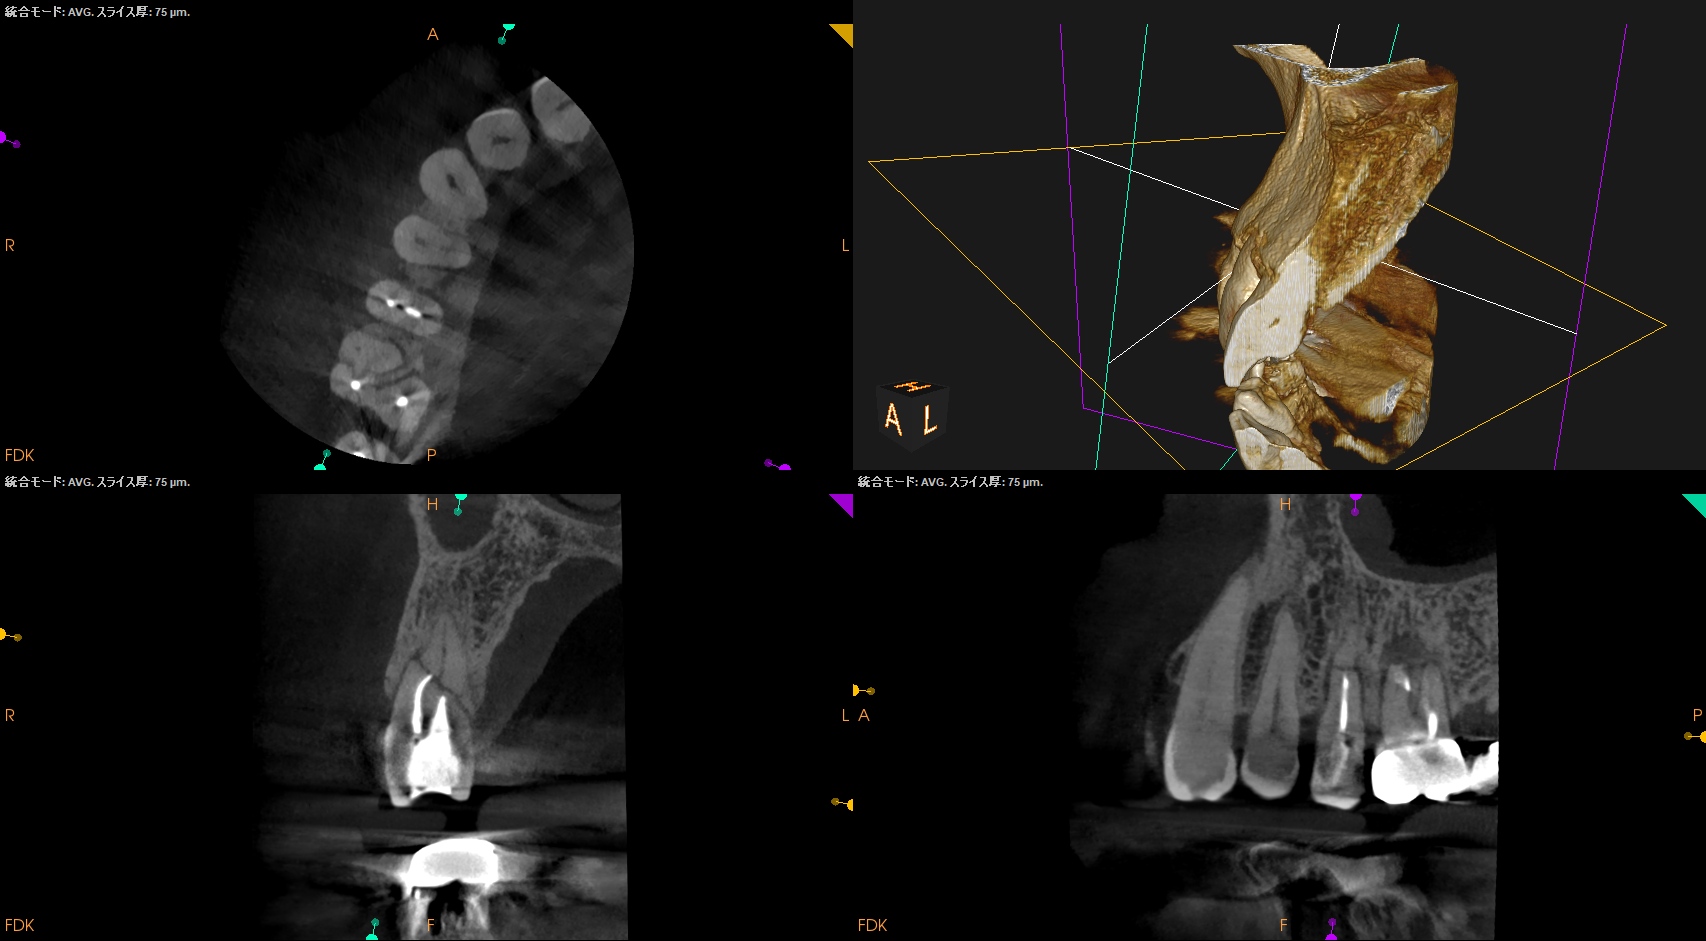

CBCT(2024.10.28)

#4

歯根の中央で水平に破断している。

ここで重要なことは破折片の口蓋側寄りの歯根には病変がないということだ。

ということは…

そこは根管治療が不要である。

治療のゴールとしては、

このような形状に落ち着くのがベストであると言えるだろう。